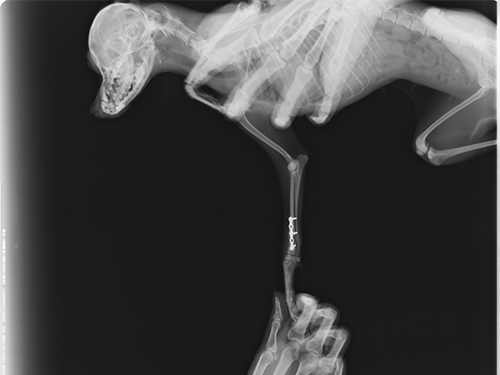

贵宾犬,5个月,雌性,免疫史全。

主诉:该犬从椅子上跳落后右前肢不能着地,稍有碰触即疼痛惨叫。CR显示该犬右前肢桡尺骨骨折,经协商后实施骨折内固定手术。三周后着地,走路无异常。一个月后痊愈。

图2:手术前右前肢侧位图